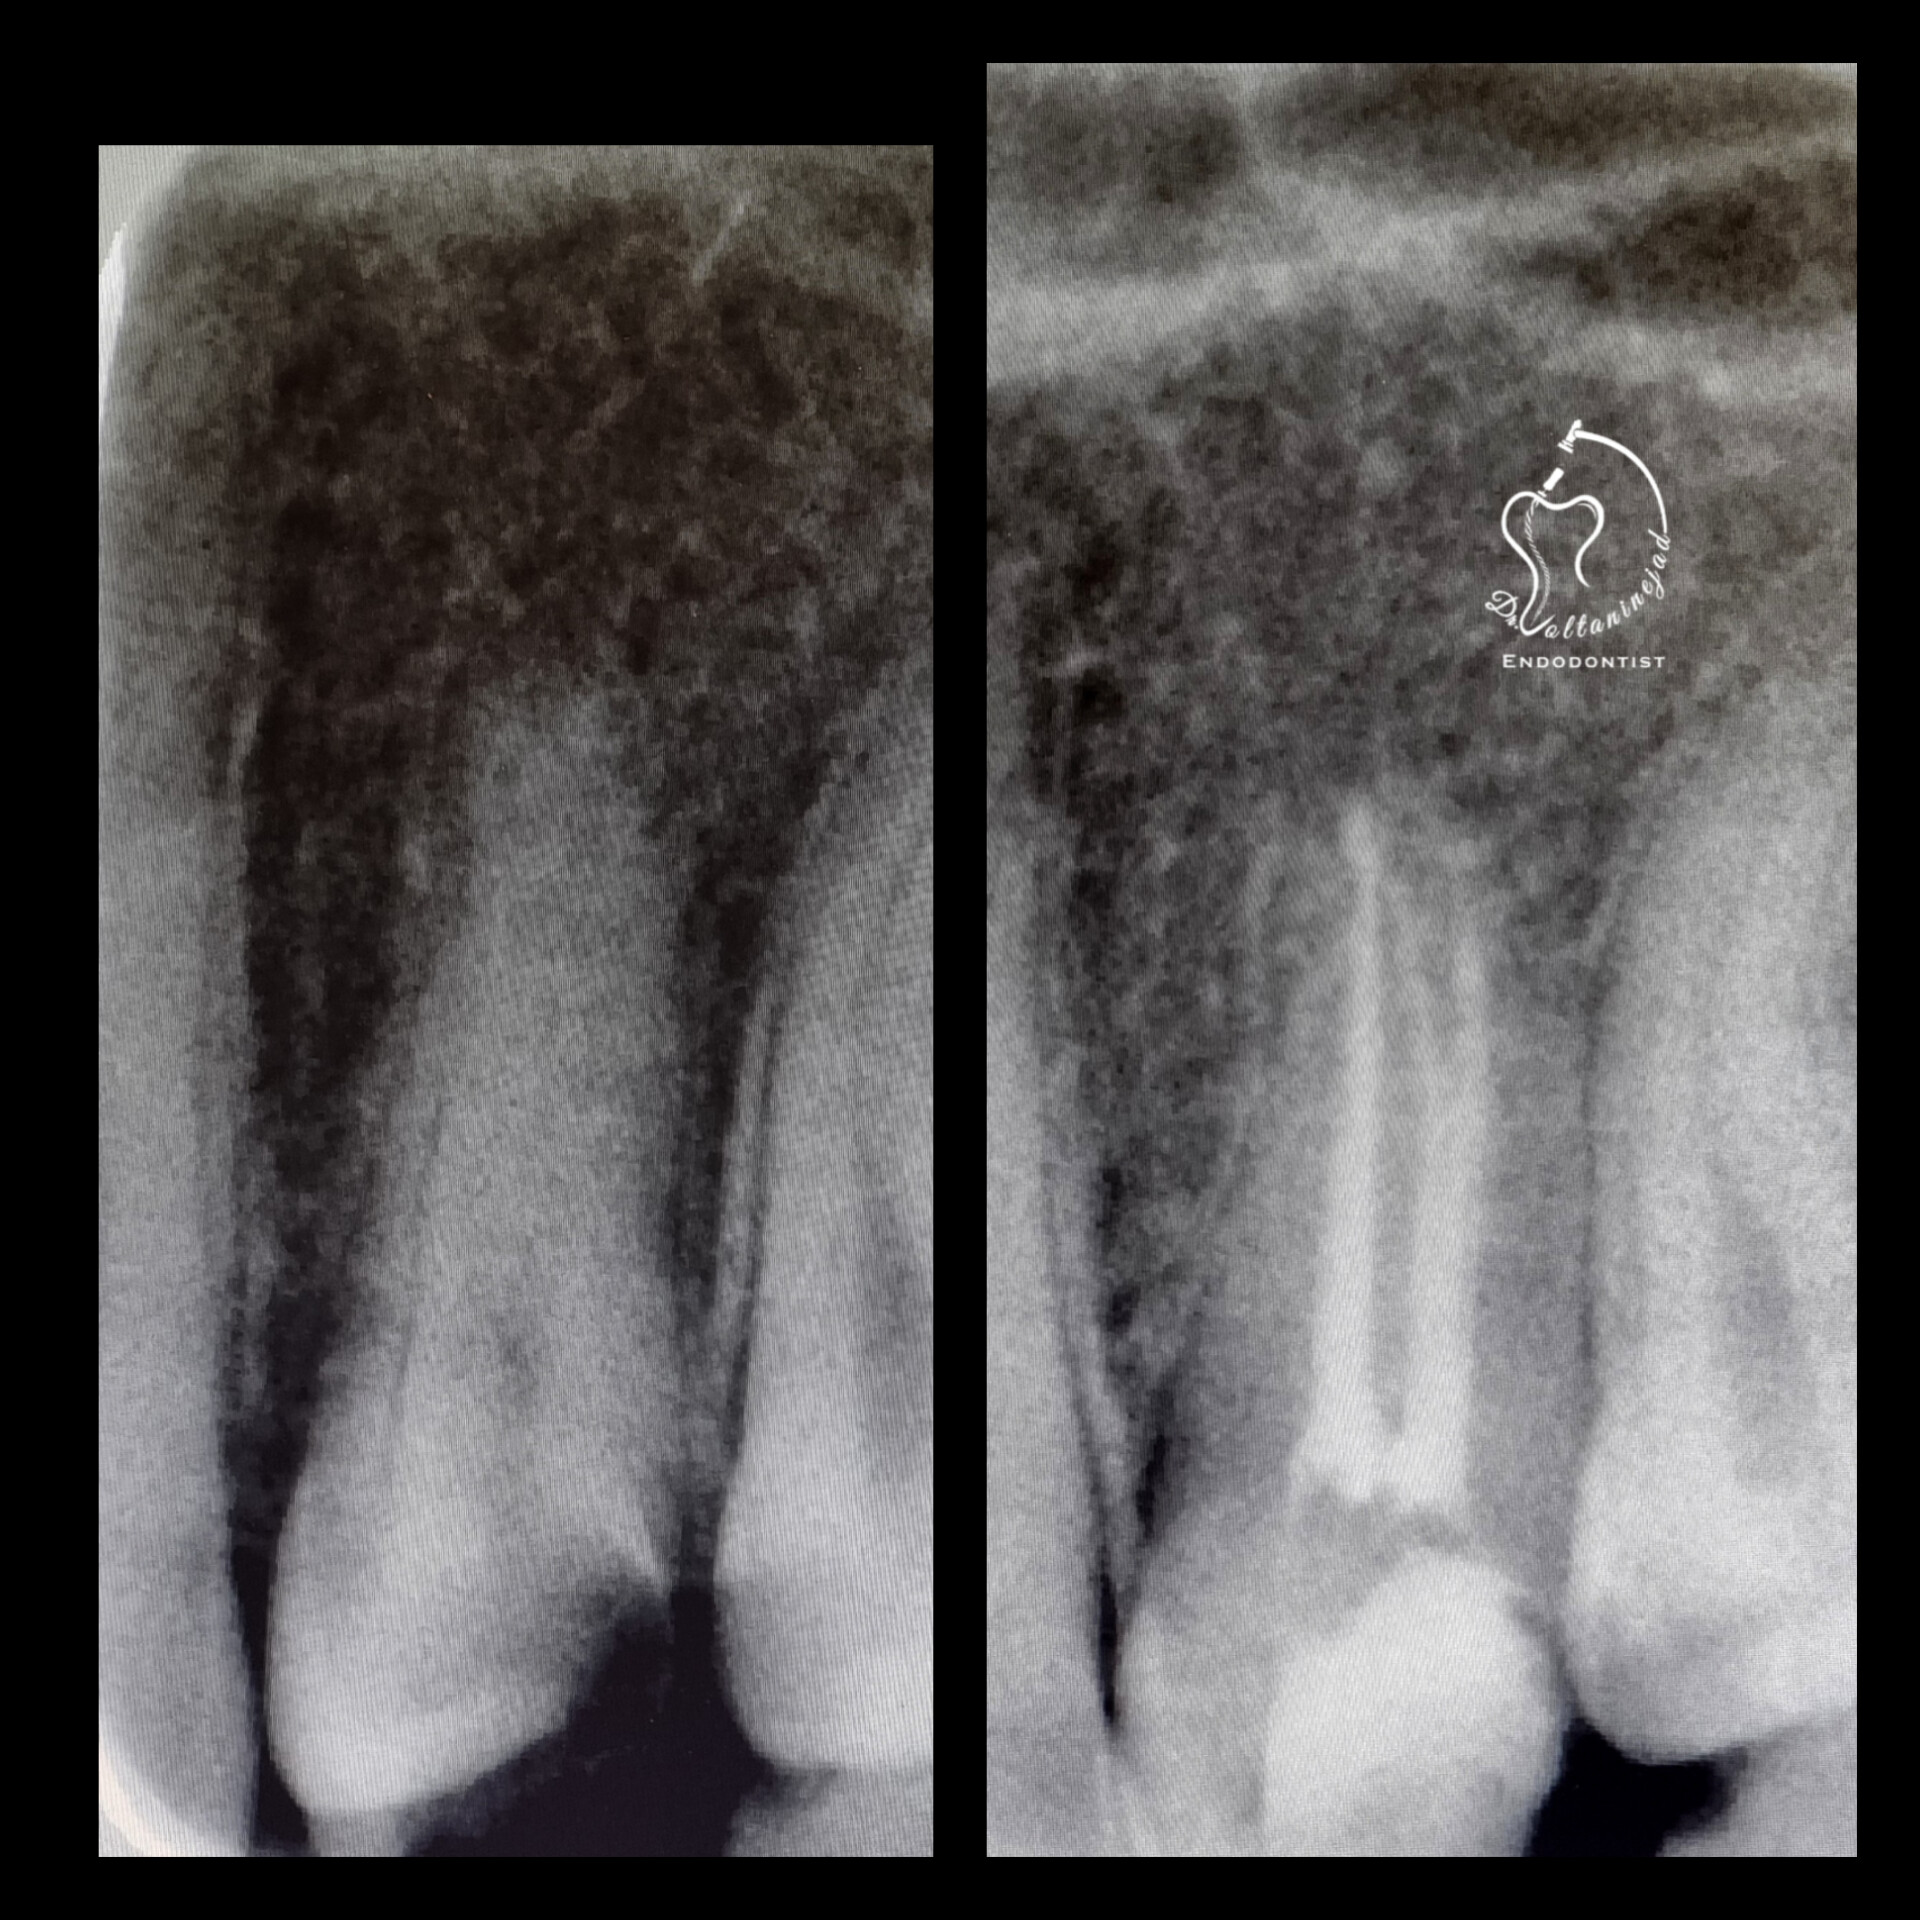

🔹 درمان ریشه دندان دائمی نابالغ با انتهای ریشه باز و آبسه مزمن در کودک ۸ ساله

• شرح کوتاه: کودک ۸ ساله با دندان دائمی نابالغ عفونی و آبسه مزمن مراجعه کرد که درمان ریشه تخصصی میکروسکوپی با موفقیت انجام شد.

• نتیجه: حذف ضایعه مقاوم و حفظ دندان به مدت طولانی.

درمان ریشه دندان نابالغ